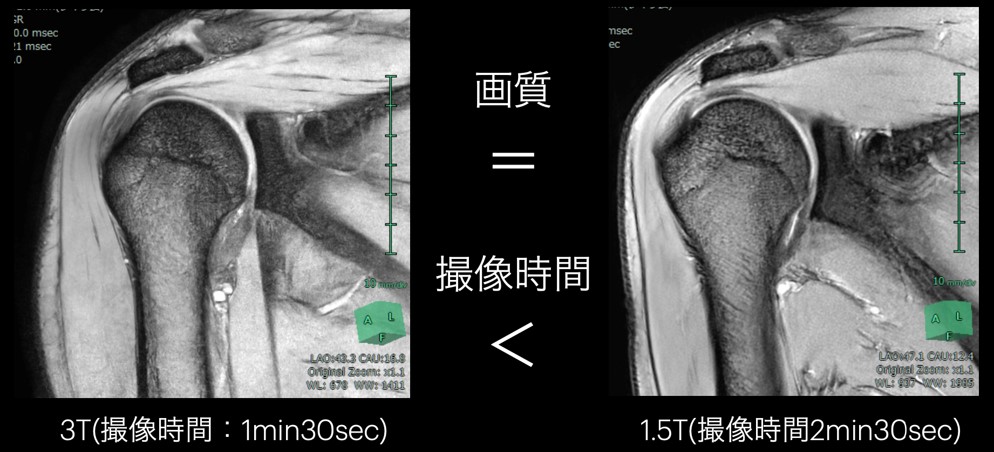

また、画質向上を目的として3Tと同等の画質を得ることも可能です。当院では四肢関節において、3T装置の検査を標準としていますが、検査の進捗度によってはSIGNA™ Victor 1.5Tの検査に切り替えることがあります。

図4に同一患者のSIGNA™ Victor1.5Tと3T装置の画像を示しますが、画質に大きな差はありません。撮像時間は若干長くかかりますが、肩関節などの四肢関節において、3Tと同等の画像を1.5Tで撮像することは今までは不可能であり、AIR™ Recon DLが搭載されたことで可能になりました。

VictorLiftUpgrade_Kitakyushu07.jpg

図4: 肩T2*WI 他社製DLR搭載3T VS 1.5T Signa Victor (左)3T (右)1.5T